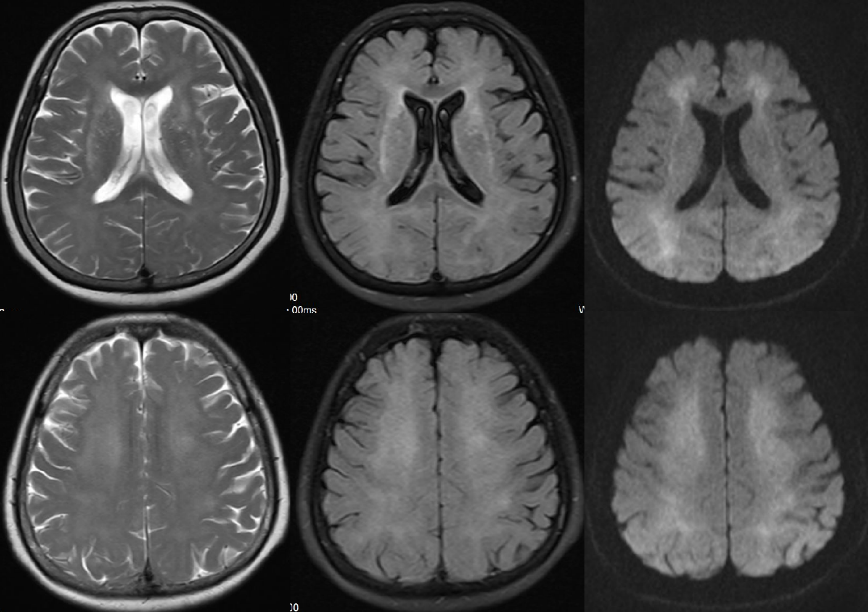

女,68 岁,一氧化碳中毒迟发性脑病,MR 表现双侧侧脑室周围白质对称性异常信号,T1WI 呈低信号,T2WI、FLAIR 及 DWI 均呈高信号